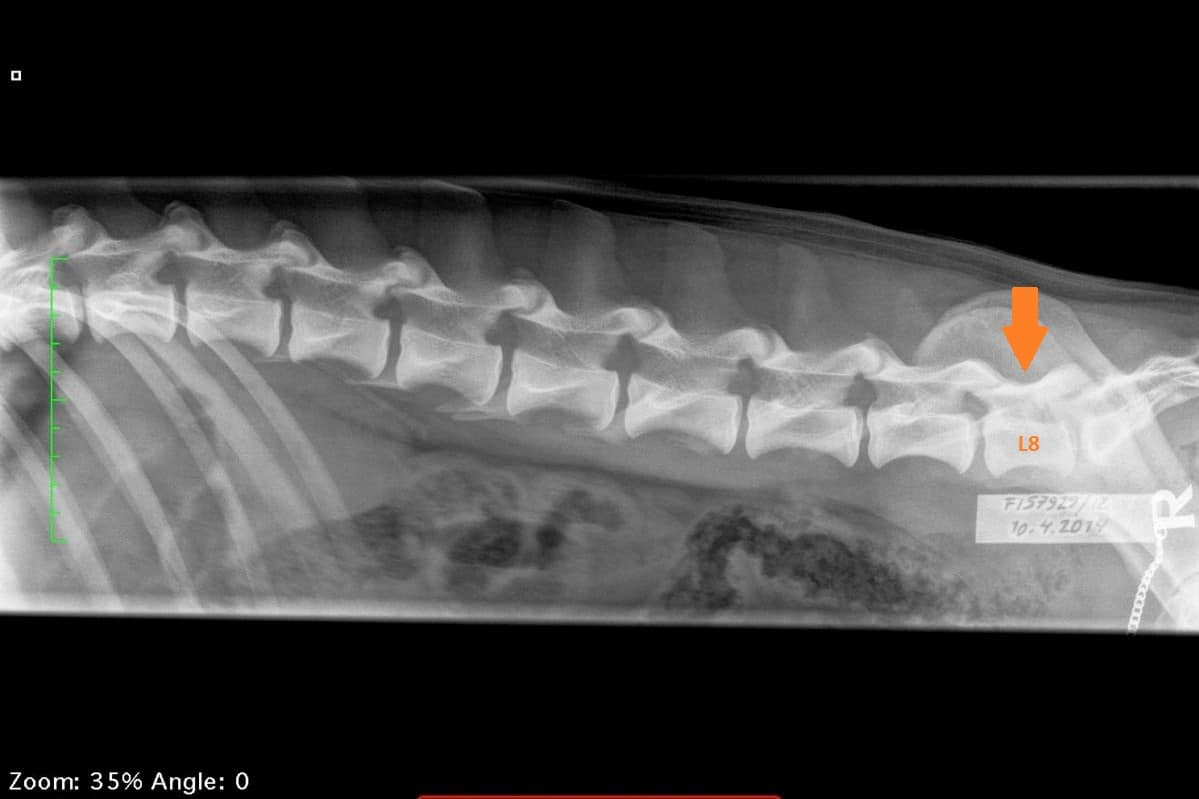

LTV4; 8 lumbar vertebras. L8 shaped like a lumbar vertebra and it has complete spinous process.